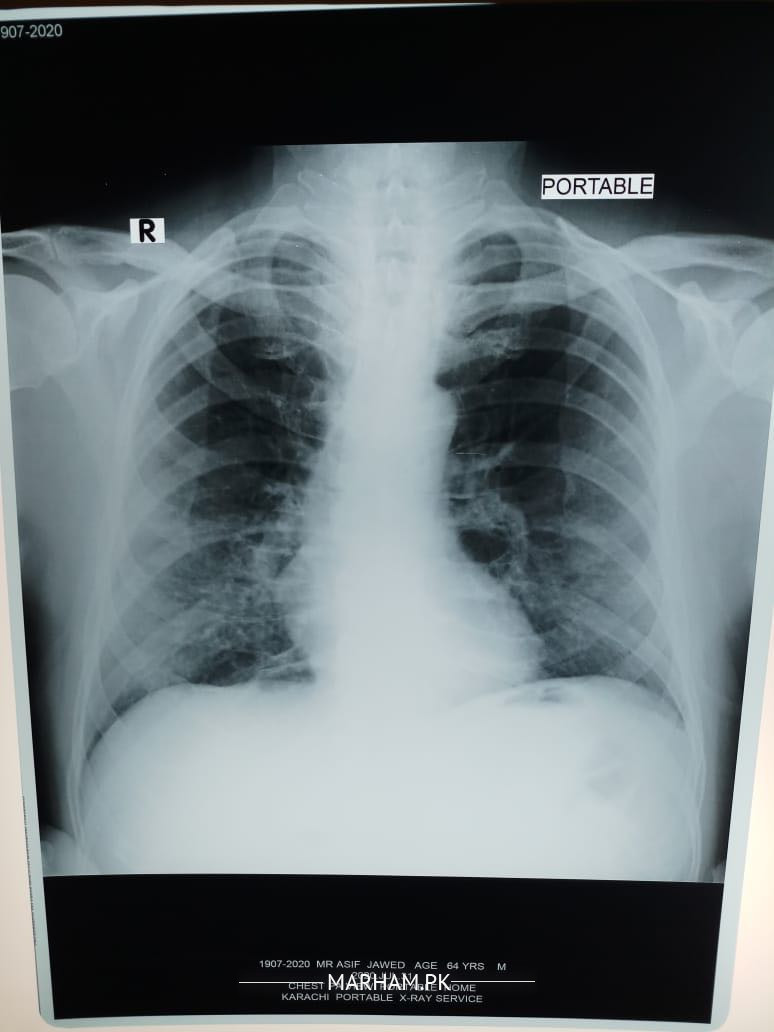

My father tested positive for corona yesterday. He has had fever 100 101, severe weakness and cough, loss of appetite etc. We got a chest extant done today and the radiologist’s report says this “â€Fibro nodulations both mid and lower zones. Rest of the lungs are clear . Cardiac size within normal limits . No evident of pleural effusion. Costophrenic angles are clear . Bony cage is intact . Conclusion. Bilateral pulmonary infection “â€. Pls advice what can be done should he be taken to the hospital?

dear the findings in x ray can be due to corona virus infection

but they can also be due to other causes

Shortness of breath no I don’t know for sure although when he speaks he starts panting and coughing after a few sentences. He’s diabetic and hypertensive both with arthritis. This is today’s xray

Can anyone pls explain what the X-ray shows? He started antibiotic on Saturday. Azomax 500 once daily with Panadol x 2 thrice a day